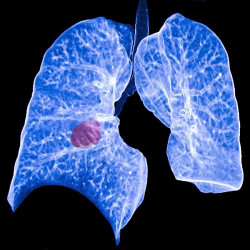

La comunidad de investigación del cáncer de pulmón, reunida virtualmente en la Conferencia Mundial IASLC 2020 sobre Cáncer de Pulmón, que se celebra en Singapur, ha ofrecido una rueda de para compartir una serie de hallazgos de investigación que examinan la intersección de COVID-19 y el cáncer de pulmón, en la que investigadores de varios países han examinado la conexión entre el cáncer de pulmón y COVID-19.